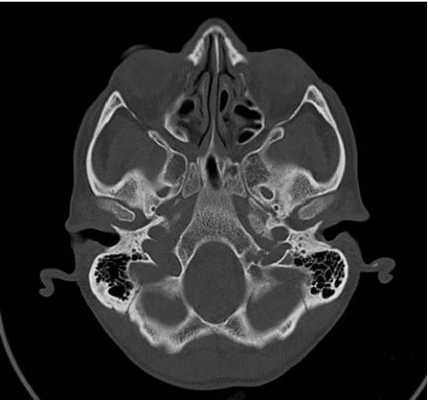

КТ основания черепа

КТ основания черепа - метод медицинской визуализации, основанный на использовании рентгеновских лучей, и применяющийся для диагностики патологических процессов, локализующихся в нижних отделах черепной коробки. Позволяет получать серии послойных снимков области интереса, толщиной от 0,5 мм, с высоким разрешением и четкостью. Благодаря этому компьютерная томография - один из самых точных и достоверных методов диагностики, незаменимый при некоторых патологиях и заболеваниях мозговой части черепа.

Основание черепа - область, образуемая затылочной, височными, решетчатой, лобной и клиновидной костями. Внутренняя поверхность данной анатомической структуры играет роль площадки, на которой покоится головной мозг. Через большое отверстие затылочной кости проходит ствол мозга. Наружная поверхность основания черепа богата нервными волокнами, кровеносными сосудами, связками и сухожилиями.